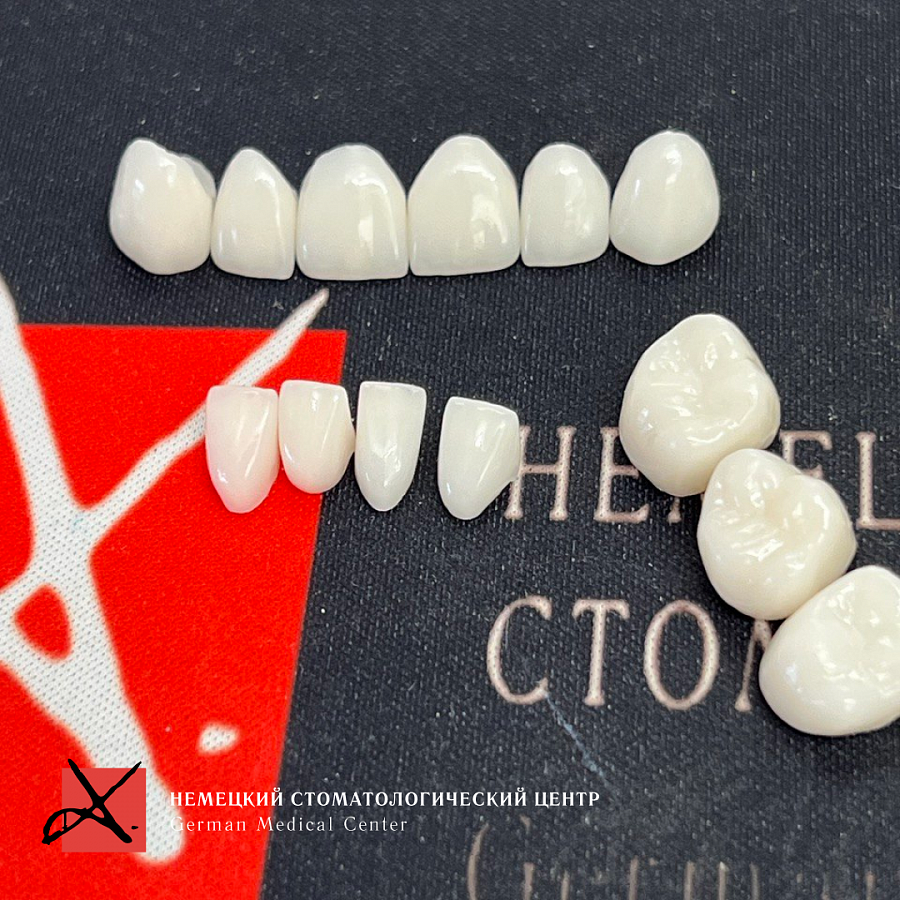

Доктора Немецкого Стоматологического Центра смогли найти решение для данного сложного случая. Была проведена комплексная реабилитация: переделаны передние зубы, частично переделаны боковые зубы, был удален несостоятельный имплантат и проведена повторная зубная имплантация. Благодаря грамотной реабилитации мы получили правильно сформированную жевательную поверхность, смыкание зубов в нужной высоте, декомпрессию сустава. В результате у пациента прошли все болевые синдромы и дискомфорт. Пациент наблюдается в Центре уже боле 2 лет, никаких сколов, проблем с суставом и жалоб больше нет.